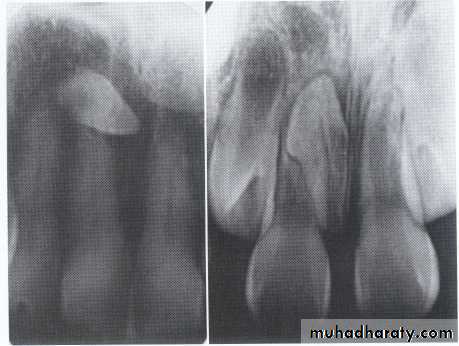

• Fusion of the left mandibular central and lateral incisors (twoindividual roots, two root canals and two joined crowns).

Gemination of right mandibular central incisor has one root, one root canal and a partially bifid dental crown.